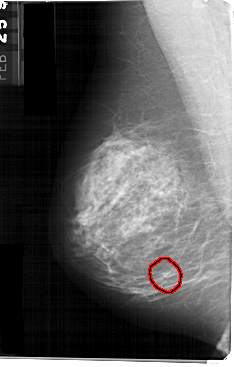

FILE: A_1368_1.LEFT_MLO.OVERLAY

TOTAL_ABNORMALITIES 1

ABNORMALITY 1

LESION_TYPE CALCIFICATION TYPE AMORPHOUS DISTRIBUTION CLUSTERED

ASSESSMENT 4

SUBTLETY 3

PATHOLOGY BENIGN

TOTAL_OUTLINES 1

LEFT_MLO LINES 5491 PIXELS_PER_LINE 3496 BITS_PER_PIXEL 12 RESOLUTION 43.5 OVERLAY